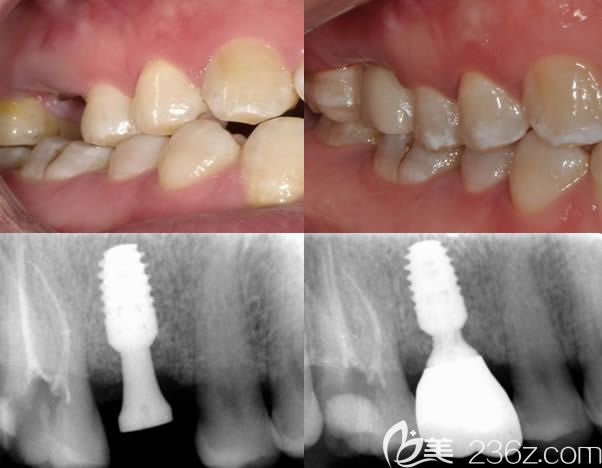

北京牙管家口腔波醫(yī)師美學種植牙案例賞析: